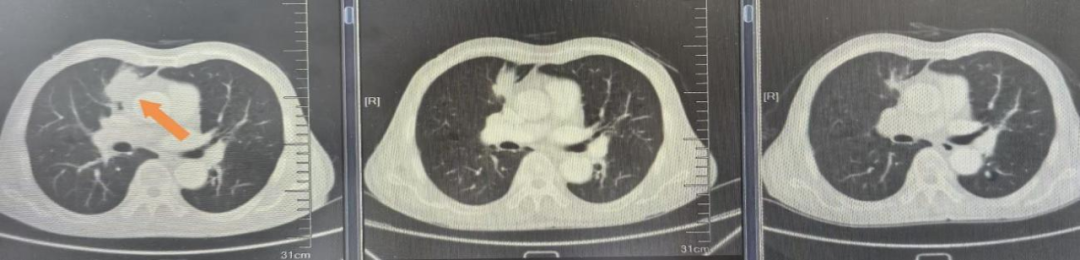

患者女,54岁,2023年11月因咳痰带血,检查肺增强CT提示右肺上叶占位,气管镜检查右肺上叶B2支气管新生物取病理,病理诊断为肺腺癌,基因检测结果:EGFR21L858R突变、TP53突变、BTK突变、ERBB2突变、KRAS扩增、TPS=60%。PET-CT提示右肺上叶肿块考虑恶性,右侧锁骨上、纵隔及右肺门淋巴结转移,临床分期为cT2aN3M0 IIIB期,PS评分1分。患者拒绝根治性放化疗,于2023.12月行伏美替尼80mg治疗,期间每2月复查评效PR,2024.8月复查肺CT肺内病灶增大提示疾病进展,PFS1=8个月;2024.8月行贝伐珠单抗联合AP方案4周期,贝伐珠单抗联合培美曲塞8周期维持治疗,2、4、6、8、10周期评效PR,2025.4月右肺上叶病灶持续增大评效PD,PFS2=8个月;2025.4月行依沃西单抗联合PC方案治疗4周期,依沃西单抗联合培美曲塞维持治疗4周期,2、4、6、8周期评效PR,PFS3超过5个月治疗持续有效中,药物安全性良好,未见相关不良反应发生。

依沃西单抗8周期疗效对比